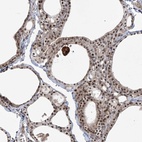

Immunohistochemical staining of human thyroid gland shows moderate nuclear positivity in glandular cells.